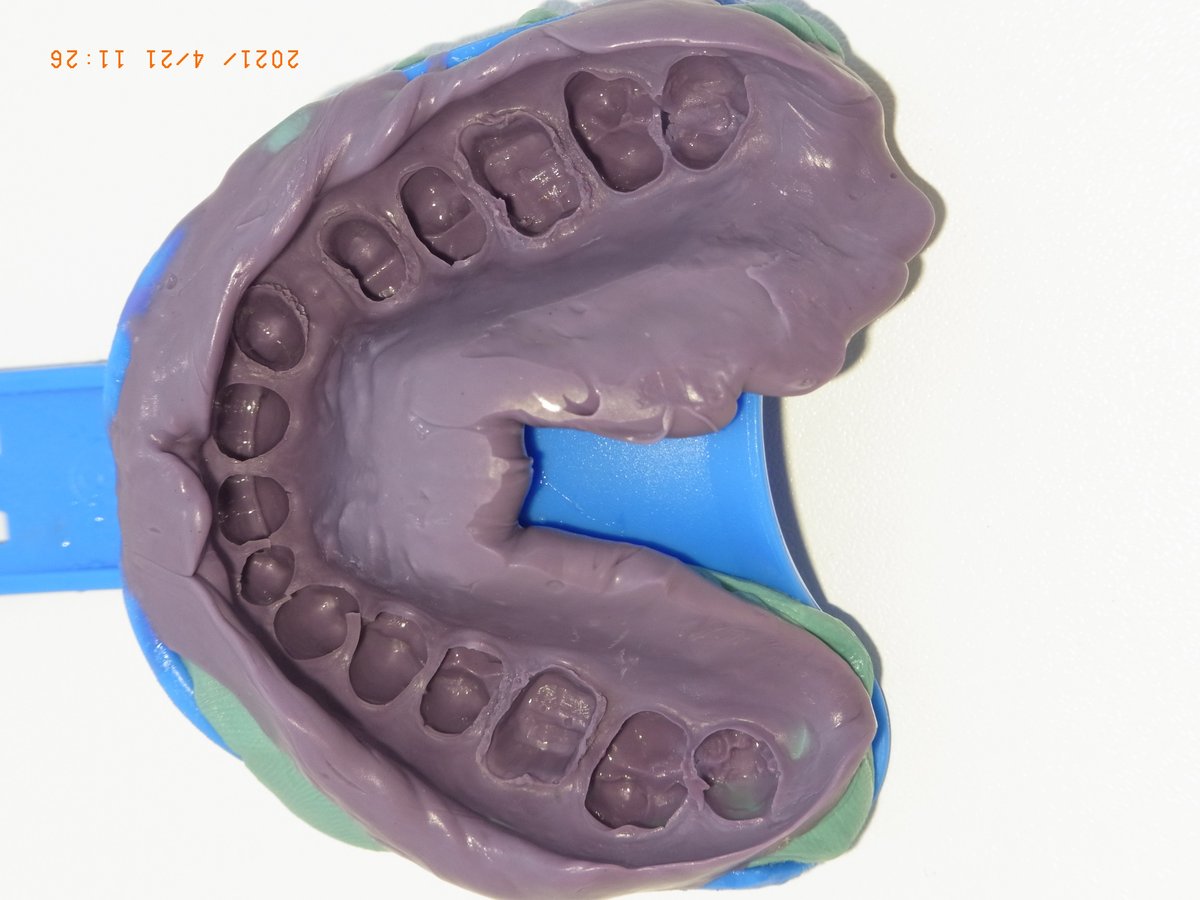

Detail der fertigen Zweitabformung: Die Stümpfe sind scharf und tief erfasst, Sulcusränder deutlich sichtbar – ohne Fahnen, ohne Lufteinschlüsse.

Gesamtansicht der fertigen Zweitabformung: vollständige Erfassung des Oberkiefers. Die beiden unabhängigen Abformungen erlauben dem Labor das Umsetzen zwischen den Modellen und decken Abformfehler frühzeitig auf.